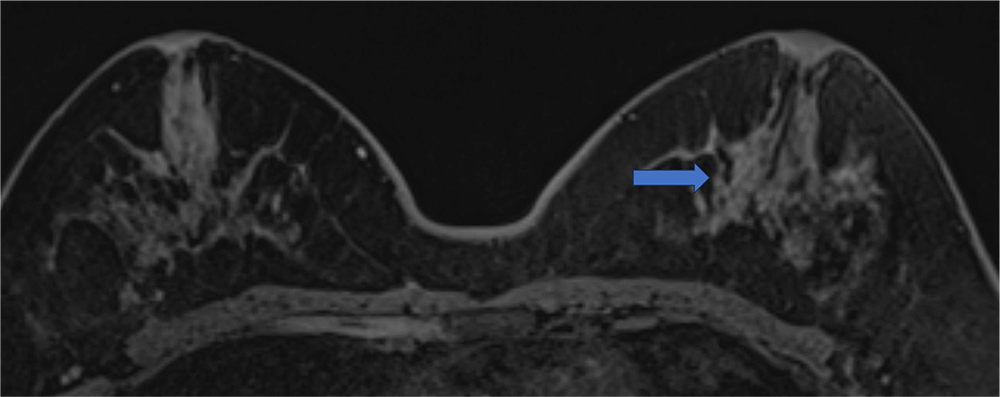

6. 造影後高分解能画像

区域性分布を示すNon mass enhancementがあるようにも見えるが、同定は困難である。